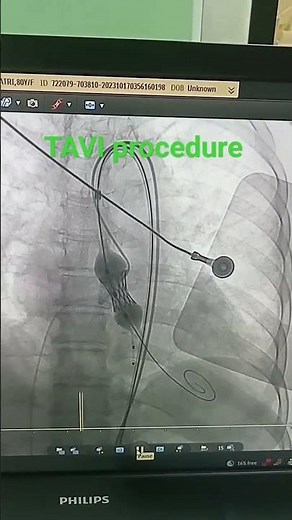

TAVI Procedure

1M views · 100 reactions | HN-TAVI software, A platform that scales with your growing needs! First TAVI Procedure at Helwan University Hospital with Dr. Yasser Sadek د/ ياسر صادق | فيليبس مصر - Philips Egypt | Facebook